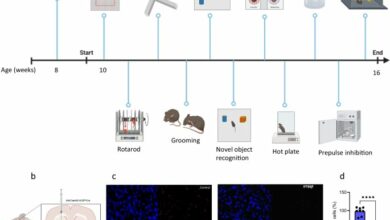

A new therapeutic target for the prevention of heart failure due to aortic stenosis

Cardiomyocyte-specific human β3AR overexpression prevents cardiomyocyte hypertrophy upon catecholamine challenge via NO/cGMP pathway. A Genetic constructs for adeno-associated virus (AAV)…